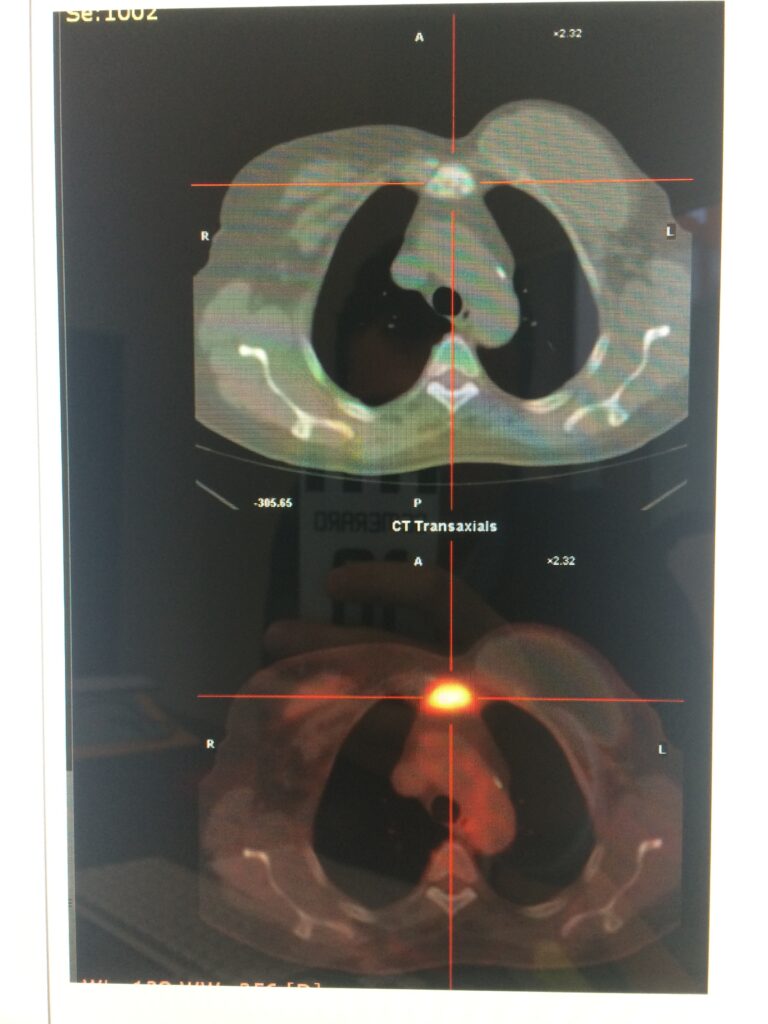

Crioablazione tumori

Termoablazione tumori